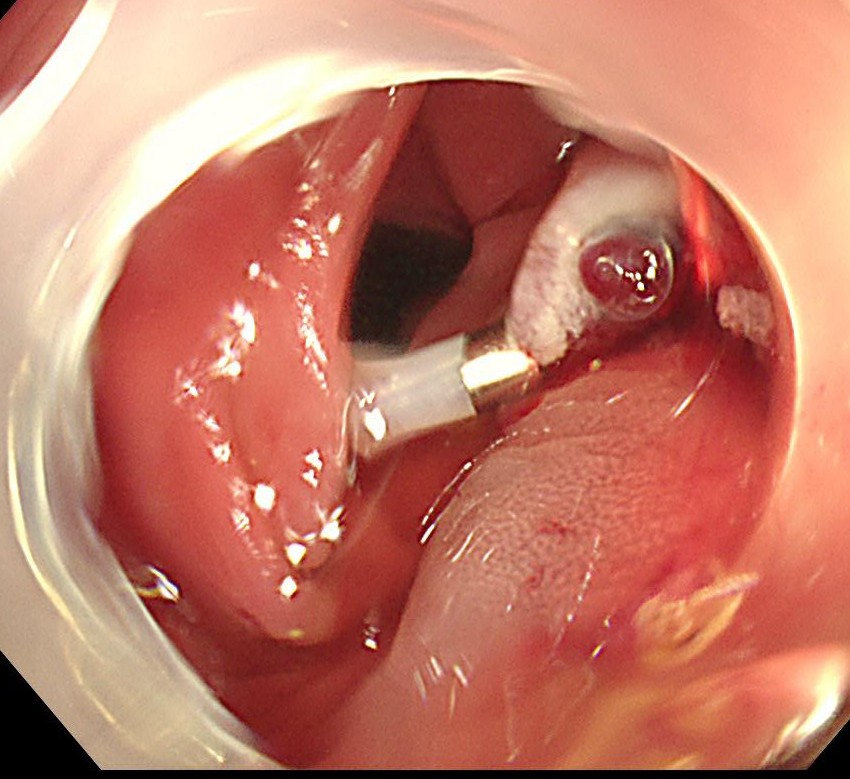

粘膜下に生理食塩水を局注し、電気メスで切除します(EMR)。

切除断端はクリップで閉鎖します。